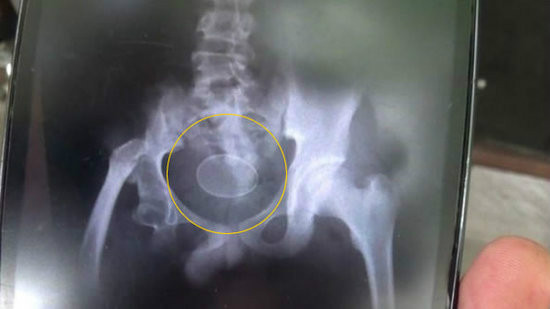

《长株潭报》株洲讯(记者杜方江通讯员梁辉)欠债没还,*债追**人恼羞成怒操起玻璃瓶从肛门处塞入长沙男子李钱缺(化名)体内。9月1日清晨,他赶到湖南省人民医院急诊科就医。

50来岁的李钱缺离异多年。8月30日,他被*债追**人从肛门强行塞入一个装花露水的玻璃瓶。从B超和CT上可清晰看到,玻璃瓶底朝下嵌在李钱缺的直肠下段,瓶内还有小半瓶液体。结直肠肛门外科医生董宏宇表示,因异物进入体内已有2天,已造成肛门括约肌损伤和肠壁严重水肿,只能通过开腹手术将异物取出。

“我们曾经收治过塞玻璃杯、手电筒的。”董宏宇提醒,肛门被塞进异物后一定要及时就医,否则导致肠破裂大出血,将危及生命。